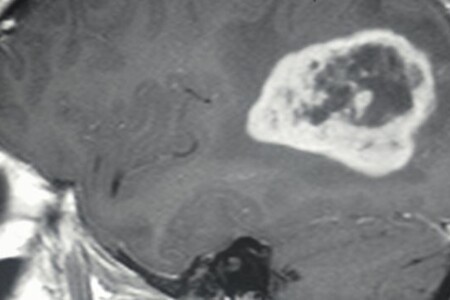

Abscesy neboli hlízy jsou ohraničená zánětlivá ložiska, která se mohou tvořit kdekoliv uvnitř těla nebo na jeho povrchu. Jejich rozměry se různí od drobných puchýřků a vřídků na kůži nebo při vlasových koříncích až po závažnější abscesy zubních lůžek nebo abscesy vnitřních orgánů, například při zánětu slepého střeva (apendixu).

4 komentáře